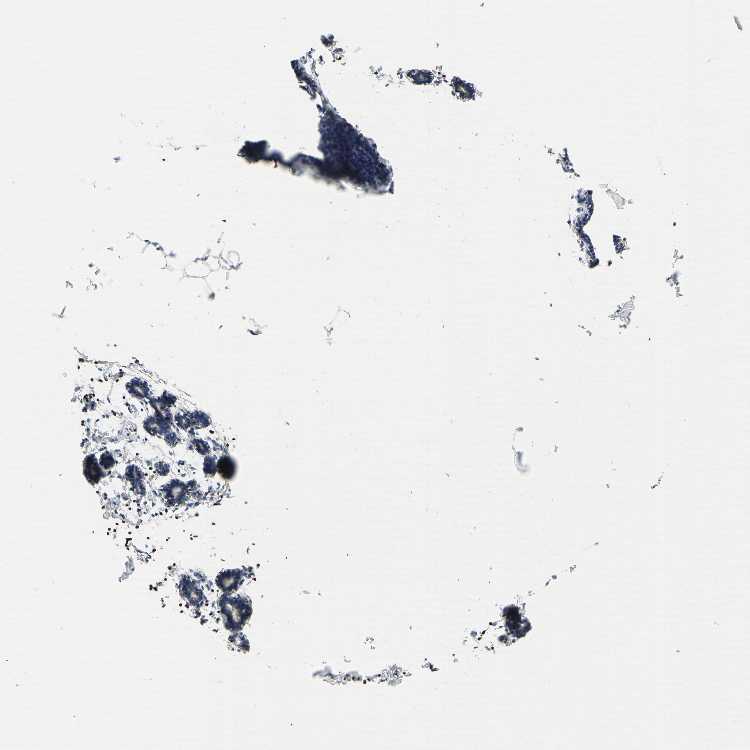

BREAST - Antibody stainingi

Antibody staining in the annotated cell types in the current human tissue is reported as not detected, low, medium, or high, based on conventional immunohistochemistry profiling in selected tissues. This score is based on the combination of the staining intensity and fraction of stained cells.

Each image is clickable and will lead to virtual microscopy that enables deeper exploration of all samples and also displays staining intensity scores, fraction scores and subcellular localization as well as patient and tissue information for each sample.

Antibody HPA002462Antibody HPA009650Antibody CAB005077

Adipocytes Not detectedHighMedium

Glandular cells Not detectedMediumLow

Myoepithelial cells Not detectedMediumMedium